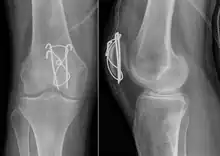

Surgery

Most patella fractures are transverse or comminuted, hence the quadriceps mechanism is disrupted and they are treated by a combination of wires in a tension band construct. This unites the fractured bones, reconstructing the straightening mechanism of the leg.[5][6]

If the patella is broken in several places, that is comminuted, then traditionally a patellectomy (removal of the whole patella) is performed in order to reconstruct the extensor mechanism and prevent the onset of an extension lag at the knee joint, resulting in instability.[5][10][11] Some surgeons however would rather opt for internal fixation.[10] A partial patellectomy is removal of only a portion of the patella, and may be carried out if at least 60% of the patella can be maintained.[10][6]